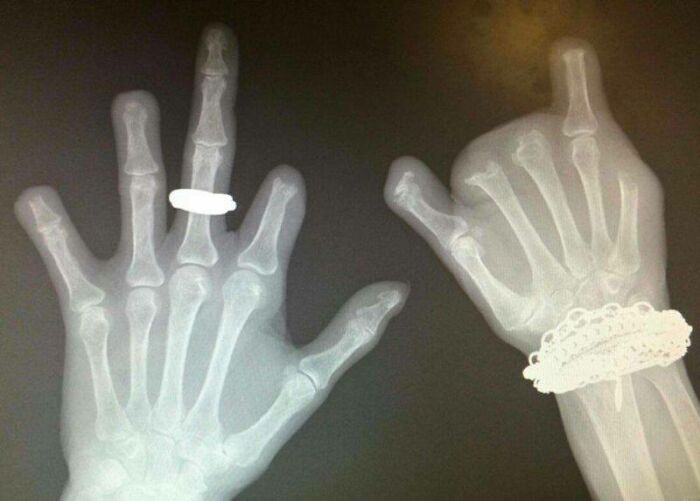

#10 Röntgen pacienta, ktorý mal dlhú históriu žuvania, olizovania a obhrýzania prstov až na kosť (To malo za následok závažné bakteriálne infekcie, ktoré museli byť liečené viacerými amputáciami.)